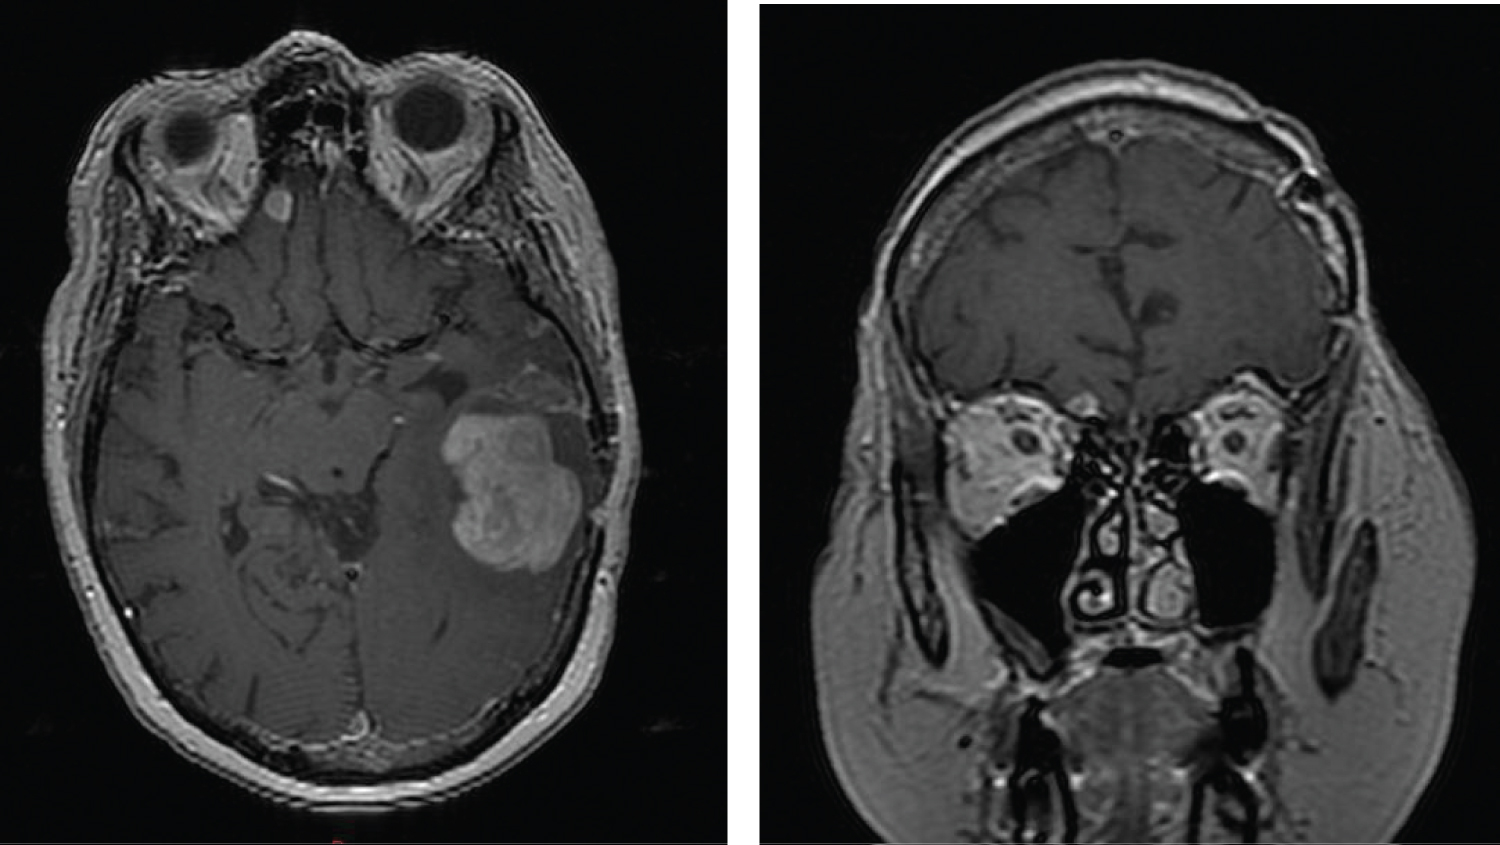

A second resection was performed and a total gross removal was achieved. As before, a histopathologic evaluation of the specimen revealed a gliosarcoma. She embarked on a second course of radiation therapy coupled with temozolomide. During her course of therapy, she was noted to have an enlarging subcutaneous nodule over the left temporal craniotomy site that initially was thought to represent developing scar tissue from her surgery. However, its persistent growth led to a third MRI that revealed a new mass in the left frontal parietal region with transdural extension of the mass through the second craniotomy site (Figure 4).

Figure 4: After resection of the second mass (Figure 3), an enlarging palpable mass was noted near the second craniotomy site. Transverse MRI images revealed a new 2.3 cm enhancing lesion contacting the dura in the left frontal parietal region with an associated 14 mm scalp nodule that represented transdural spread of disease through the second craniotomy site. The coronal images show the new enhancing lesion and adjacent scalp nodule remote from the previous intraparenchymal operative bed in the left temporal lobe. View Figure 4